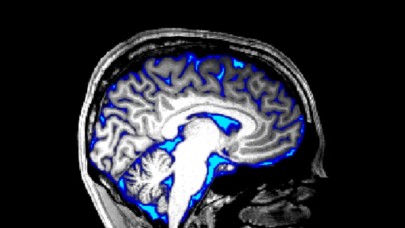

Omurilik sıvısı ile beyni iyileştirecekler!